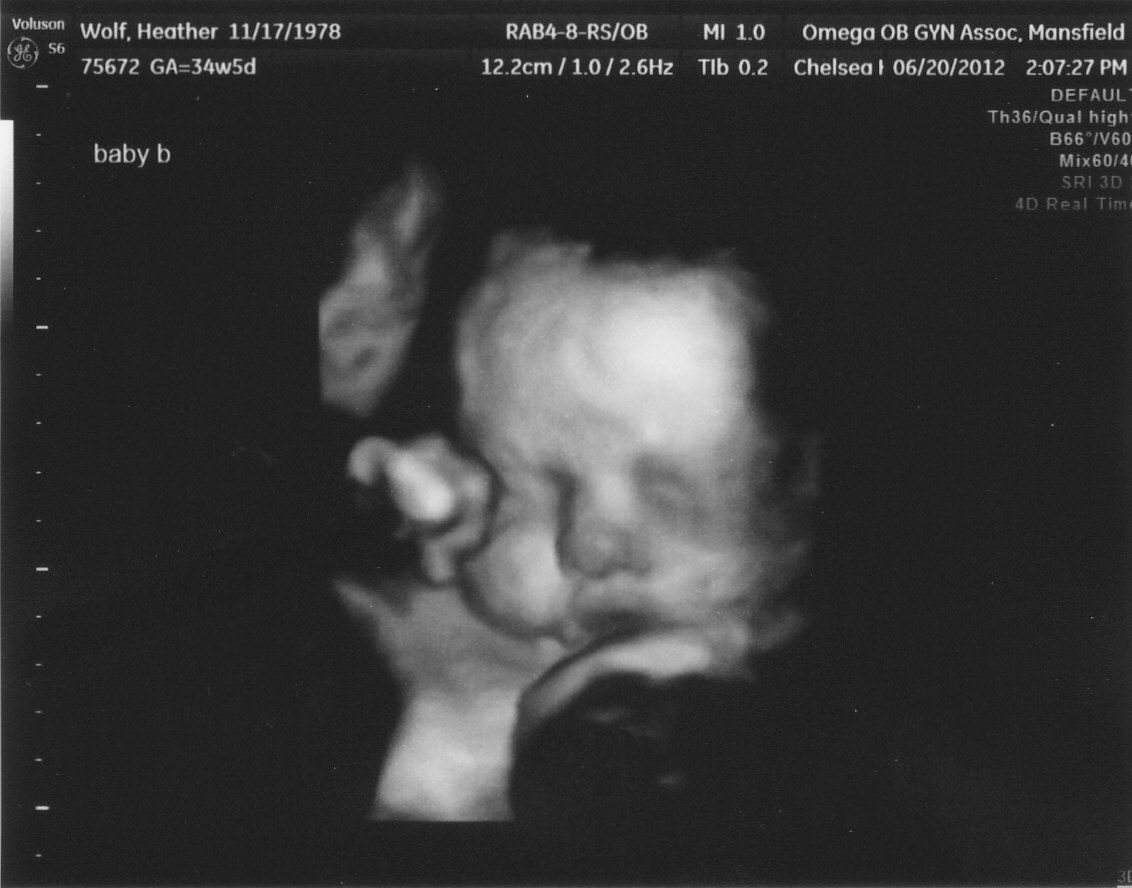

Baby boy was cooperating this time and we got a great picture of him. Baby girl had her chance a few days ago and decided she didn't want her picture taken this time.

| here he is looking left and with his hand up by his eye =) such a sweetie! |